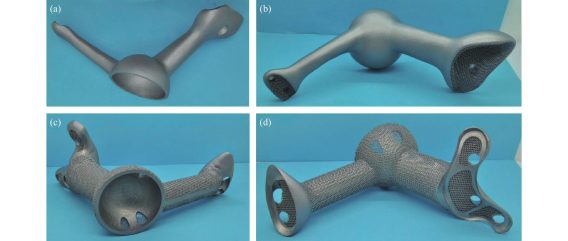

Được sử dụng để chế tạo tấm thép, ốc vít, khớp nối, và thậm chí cả xương nhân tạo, hợp kim titan hầu như không được cơ thể con người chấp nhận trong nhiều thập kỷ, điều này đã từng là vấn đề với các kim loại khác từ lâu, vậy tại sao hợp kim titan có thể xâm nhập vào cơ thể con người và cùng tồn tại một cách hòa bình? Khoa học đằng sau điều này sâu sắc hơn bạn nghĩ rất nhiều.

Hợp kim titan được sử dụng phổ biến nhất trong phẫu thuật gãy xương, ví dụ, gãy xương vụn cần phải dùng nẹp thép và vít để ghép các xương gãy lại với nhau, một ví dụ khác là hoại tử chỏm xương đùi ở người cao tuổi, cần thay khớp nhân tạo, trong đó hợp kim titan là vật liệu được ưu tiên, các dị tật bẩm sinh, vẹo cột sống và tái tạo sau khi cắt bỏ khối u xương cũng rất cần thiết.

Vậy, người ta có thể hỏi, nếu nó tốt như vậy, tại sao nó không được sử dụng trong tất cả các ca phẫu thuật? Lý do rất đơn giản: hợp kim titan, tuy tuyệt vời, nhưng lại đắt đỏ, chi phí tinh chế và xử lý cao, và rào cản kỹ thuật gia nhập thị trường cũng không hề thấp, hơn nữa, nó không phải là giải pháp tối ưu, đối với một số ứng dụng, chẳng hạn như cấy ghép nha khoa và stent tim, việc lựa chọn vật liệu phụ thuộc vào tình huống cụ thể.